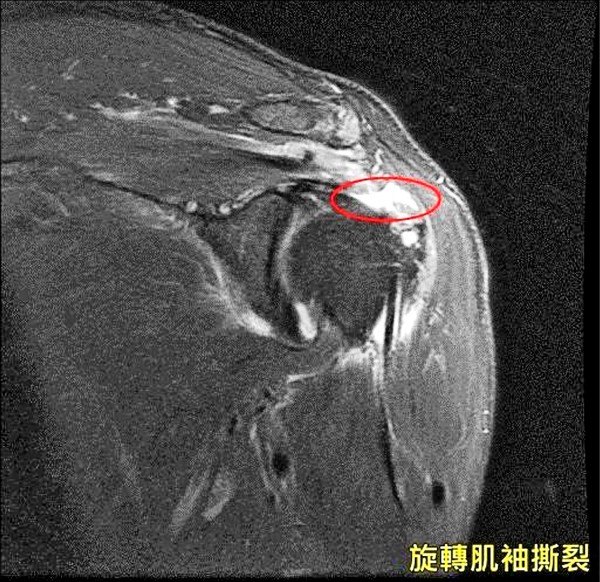

肩旋轉袖斷裂 肩袖撕裂 Rotator Cuff Tear

醫病 6旬婦肩痛以為50肩竟是旋轉肌袖撕裂作祟 即時新聞 自由健康網

旋轉肌袖撕裂多需手術修復 即時新聞 自由健康網